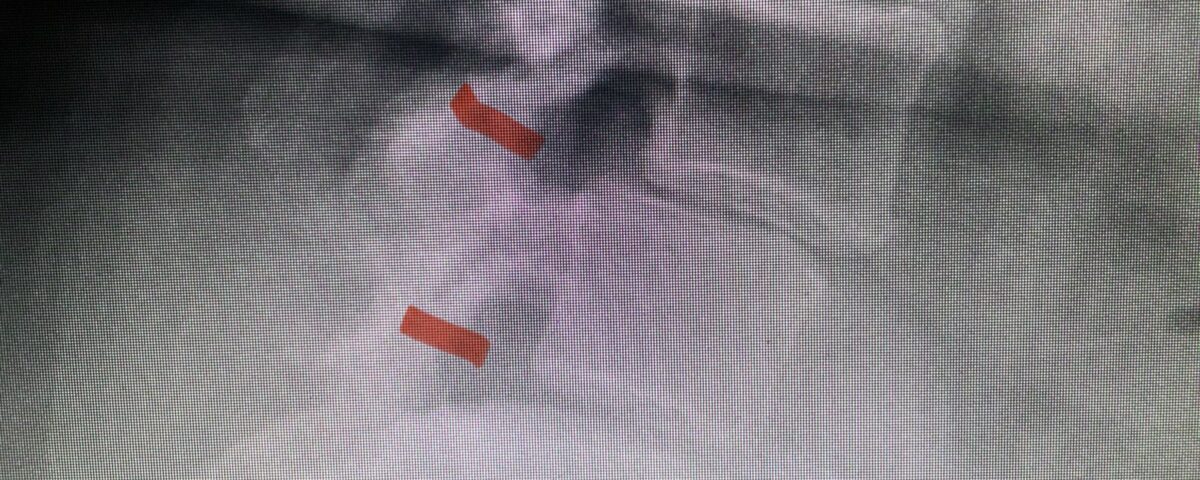

The next patient is a 56-year-old morbidly obese female who had progressive leg pain and weakness. She was over 320 lbs and did not have diabetes either. On MRI she had a massive disc herniation spanning the L3-4 and L-4 interspaces, centered behind the L4 vertebral body (Fig 3A and B). She also had an L4-5 spondylolisthesis. There were opinions that the disc emanated from the L3-4 disc space, but because of spondylolisthesis and on careful inspection of the MRI, there was a high chance the disc herniation had instead emanated from L4-5 (Fig 4). She had conservative treatment including epidurals but had worsening strength and numbness. She was scheduled electively for surgery, but then fell, and broke her ankle. She could not walk, particularly due to the pain down her leg. She was taken to the operating room urgently after she was cleared medically. She had no issues cardiologically and was taken to the operating room. The patient underwent a laminectomy that extended above the L3-4 disc space to below the L4-5 disc space. We encountered mainly centered on the left at the level of the L4 vertebral body and massive disc herniation that created a huge cavity in the lumbar canal. It was covered in an interesting thin membrane that we dissected off the disc herniation (Fig 5). Postoperatively the patient did experience significant relief of pain, but some improvement of strength. In combination with the ankle fracture and the extent of preoperative weakness, the patient required extensive rehab. The patient also developed a seroma and some wound drainage issues that were treated locally.

Fig 4: Sagittal T2-weighted lumbar MRI demonstrating an L4-5 grade 1 spondylolisthesis with obvious emanation of the disc herniation from the L4-5 level (red arrow)